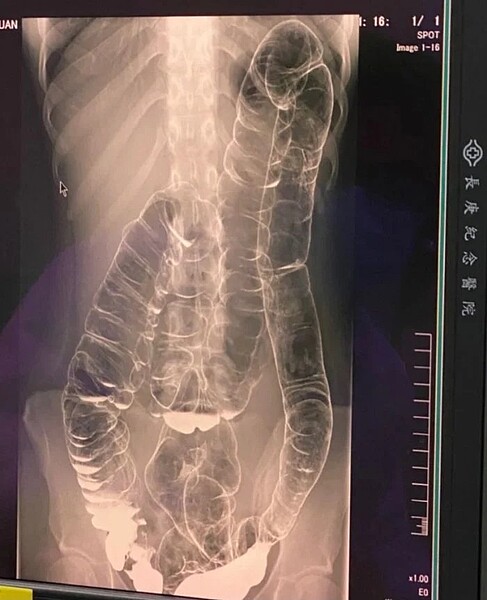

便祕是現代人常會遇到的問題,一位女大生就在網上發文表示,她從小有很嚴重的便秘問題,沒想到照了X光檢查後驚訝發現,她的大腸「超級長」,居然長到擠到心臟處,照片曝光後引起網上熱烈討論。

一位女大生從小有很嚴重的便秘問題,沒想到照X光檢查後驚訝發現,她的大腸居然長到擠到心臟處。圖/擷取自Dcard

後來原PO自己查閱相關書籍,重新求醫,希望能做鋇劑攝影,沒想到結果出來驚訝發現,她的大腸已經長到擠到心臟處,且最後一段腸子已經沒有皺摺,推測是長年糞便累積在那一段的關係,而唯一的解決辦法是將整付大腸切掉,由於她實在擔心留下後遺症,才在網上發文詢問是否有人有相關經驗。